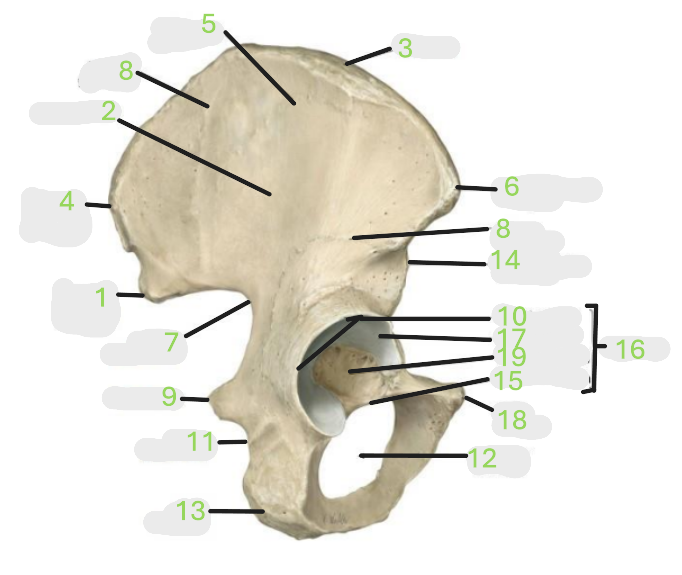

Where is the posterior inferior iliac spine

1

Where is the gluteal surface

2

Where is the iliac crest

3

Where is the posterior superior iliac spine

4

Where is the anterior gluteal line

5

Where is the anterior superior iliac spine

6

Where is the greater sciatic notch

7

Where is the inferior gluteal line

8

Where is the ischial spine

9

Where is the acetabular rim

10

Where is the lesser sciatic notch

11

Where is the obturator foramen

12

Where is the ischial tuberosity

13

Where is the anterior inferior iliac spine

14

Where is the acetabular notch

15

Where is the acetabulum

16

Where is the lunate surface

17

Where is the pubic tubercle

18

Where is the acetabular fossa

19